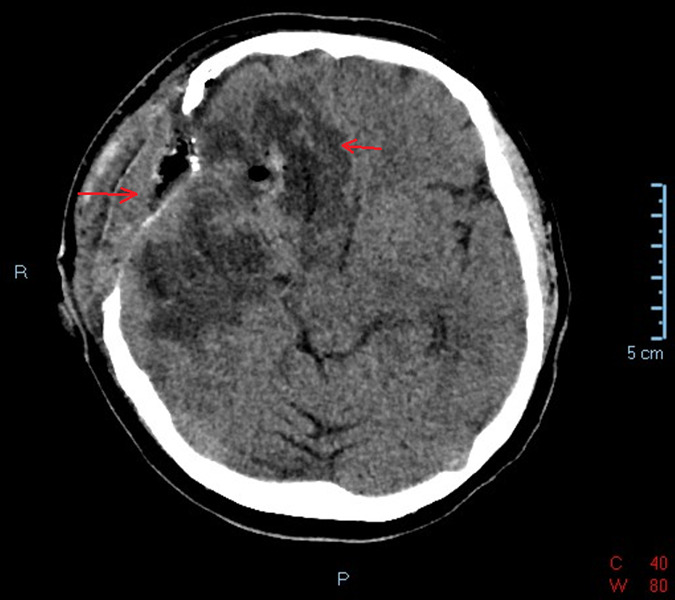

Glioblastoma represents the most common and aggressive primary malignant central nervous system tumor, often manifesting with unusual signs. This case report highlights a patient diagnosed with glioblastoma following an unusual cardiac presentation, with syncopes, sinus bradycardia, and atrial bigeminy. A 51-year-old female, brought to the emergency room after experiencing repeated syncope episodes, displayed neurological deficits upon examination. Noteworthy, she presented abnormal ECG showing sinus bradycardia and atrial bigeminy. Following the diagnostic procedure, a tumor was identified with indication to surgical removal. A subtotal tumor resection was obtained and the morphopathology examination led to a glioblastoma diagnosis. Interestingly, post-operatively, the ECG was completely normalized. However, the patient experienced complications, consisting of a massive thromboembolism. While sporadic cases describe unusual glioblastoma manifestations, this report is unique in showcasing atrial bigeminy, among other ECG manifestation. The remission of atrial bigeminy post-operatively suggests its association with the glioblastoma. Tumor localization in the basal ganglia is crucial in understanding such manifestations. Idiopathic cardiac manifestations should not be disregarded, holding potential relevance in central nervous system etiology considerations.